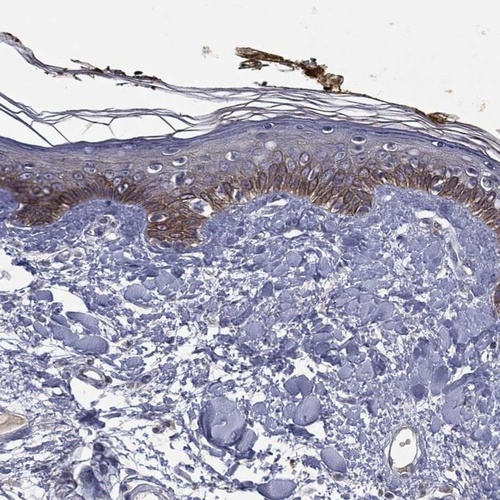

Immunohistochemical staining of human skin shows moderate cytoplasmic positivity in keratinocytes.